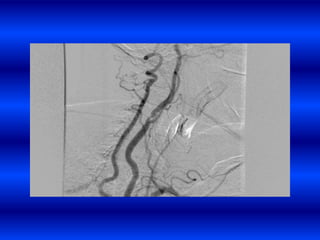

Hemorragia por anticoagulantes

HIC Post ttocon t-PA